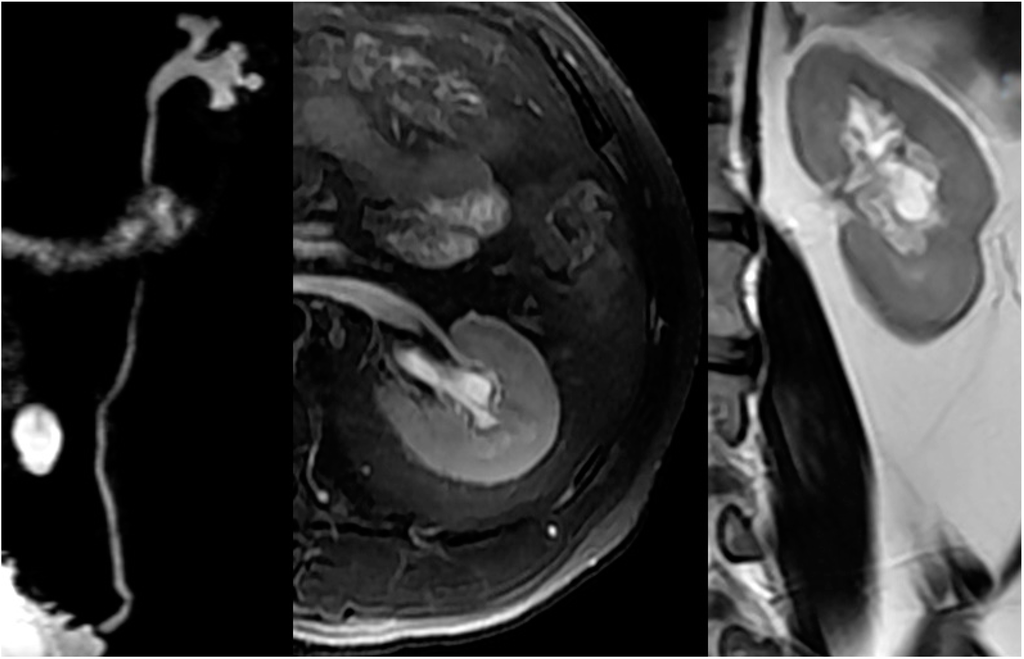

2.4. Upper Urinary Tract Imaging

2.4.1. Upper Urinary Tract Dilation (UUTD)

- Liao, L.M.; Zhang, F.; Chen, G. New grading system for upper urinary tract dilation using magnetic resonance urography in patients with neurogenic bladder. BMC Urol. 2014, 14, 38–45. [Google Scholar] [CrossRef] [PubMed]